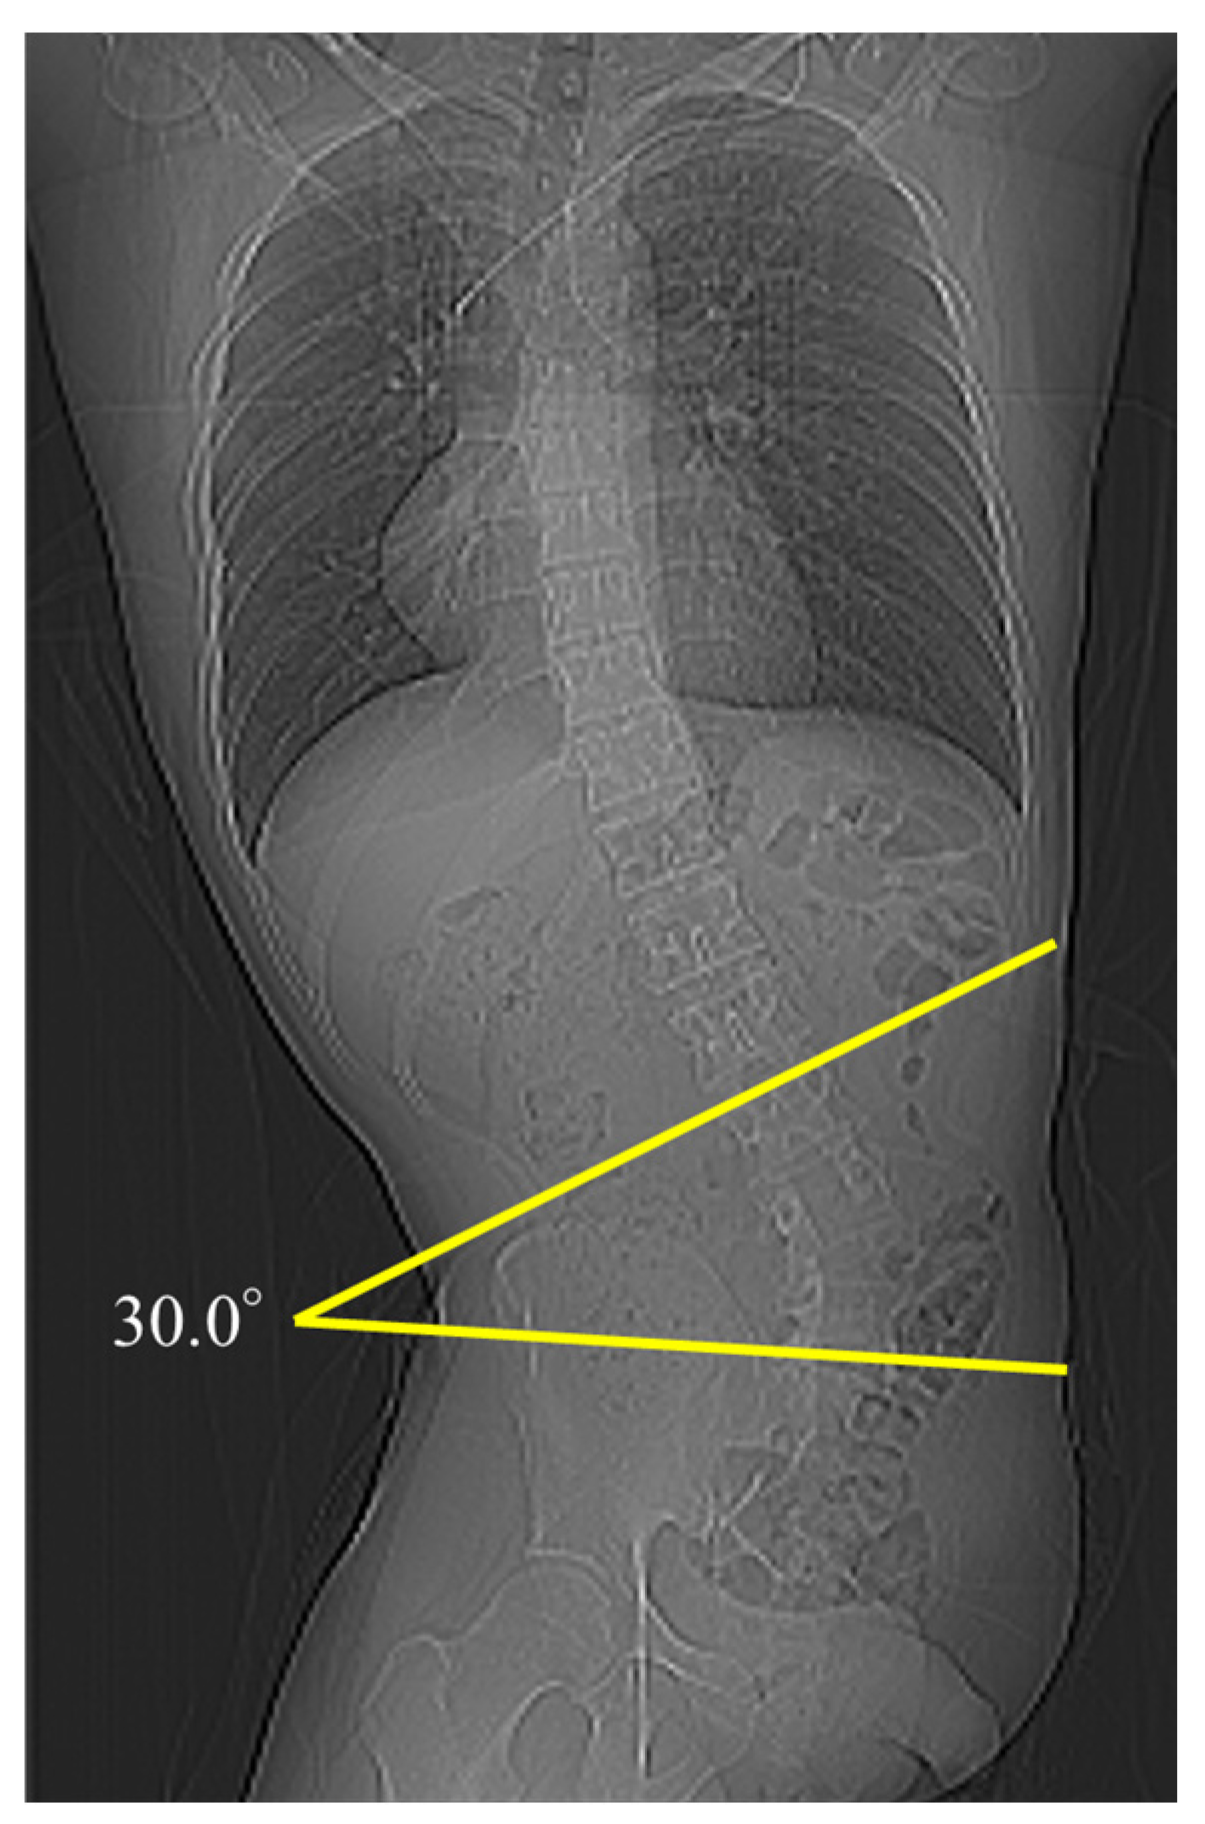

2.2. Parameter Measurements